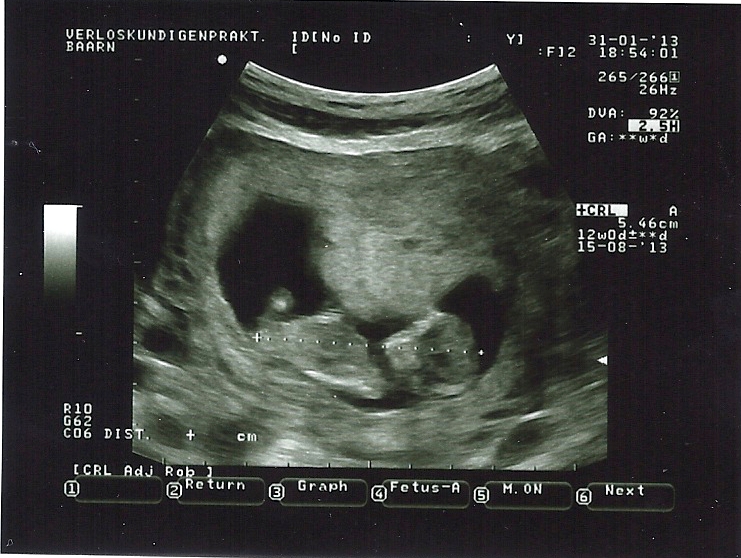

I am not sure if I see a nub in one of these pictures. Maybe the first and last? Any ideas? My mw is leaning towards girl, but on screen it looked a lot clearer than on these photo's... This was this evening, exactly 12w. Thank you for taking a look!

Attachment 8545